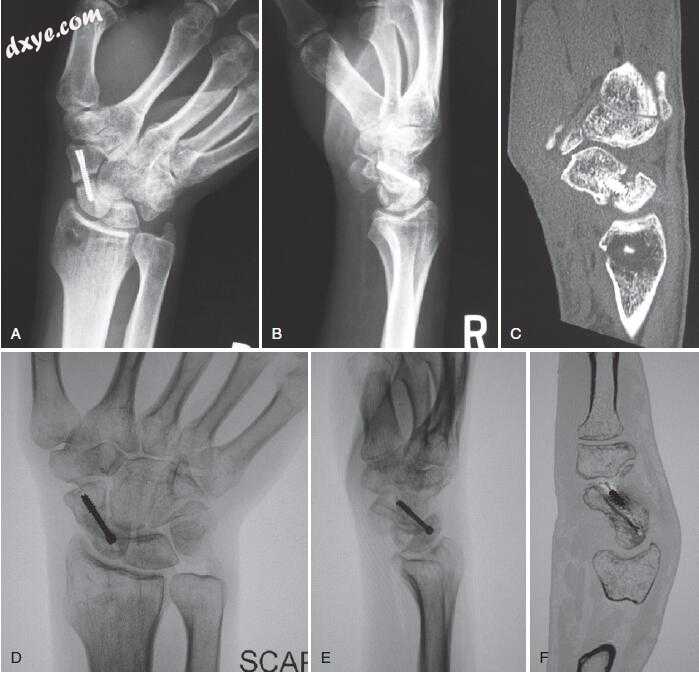

28.jpg

图.28 A,腕骨斜位X线片显示舟骨骨不连,试图切开复位内固定。 B,侧位腕部X光片。 C,计算机断层扫描(CT),矢状面扫描。 手术后12周,舟骨和侧位(E)X线片和矢状CT扫描(F)显示愈合。 (Courtesy of Scott W. Wolfe, MD.)